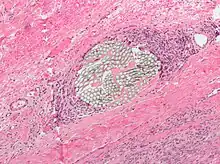

Natural absorbable: includes plain catgut, chromic catgut and fast catgut which are all produced from the collagen extracted from bovine intestines. They are all polyfilaments which have different degradations times ranging from 3–28 days.[2] This material is often used for body tissue with low mechanical or shearing force and rapid healing time.